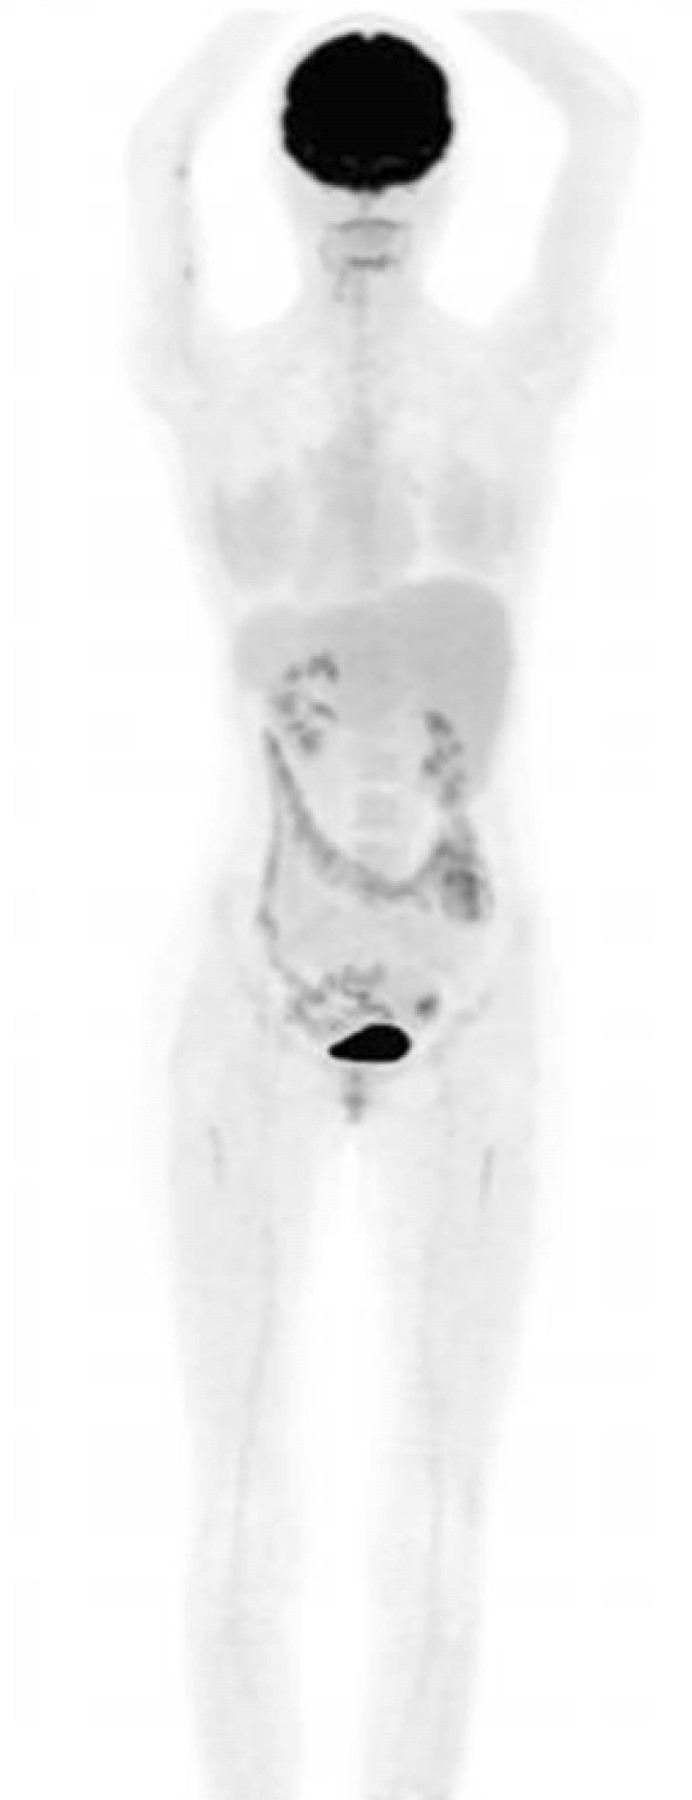

Introducción: el sarcoma mieloide, también conocido como sarcoma granulocítico o cloroma, es una neoplasia maligna resultante de la infiltración de células mieloides inmaduras en tejidos extramedulares, con una incidencia estimada de 2.5-9.1% en pacientes con leucemia mieloide aguda (LMA). El corazón es un sitio poco común de aparición (< 1%). Actualmente, no existen pautas diagnósticas ni de tratamiento firmemente establecidas para esta condición. Caso clínico: paciente femenino de 21 años con antecedente de leucemia mieloide aguda (translocación 9:11), diagnosticada a los 16 años. Tras recibir quimioterapia logró la remisión en octubre de 2019. Fue referida para seguimiento en diciembre de 2021, presentando síndrome consuntivo, palpitaciones y disnea (NYHA II). Conclusiones: este caso resalta la rareza del sarcoma mieloide cardiaco y subraya la necesidad de utilizar imagenología multimodal en el diagnóstico y seguimiento. Además, destaca la relevancia de establecer rutas asistenciales especializadas con una perspectiva cardio-onco-hematológica en México.

Figura 1